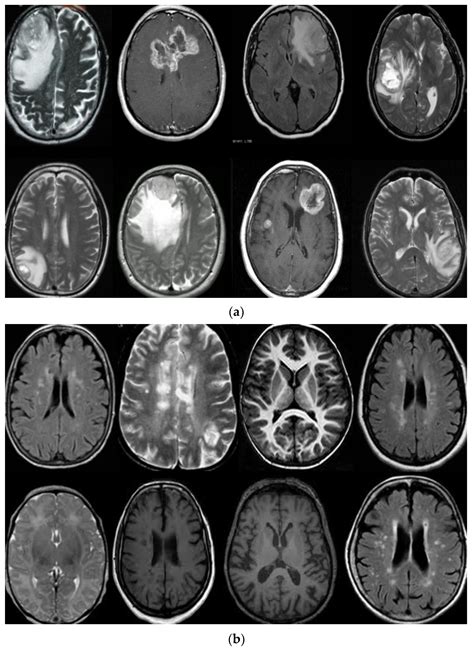

When a physician suspects an abnormality within the skull, a Brain Neoplasm MRI is the gold standard diagnostic tool used to visualize the intricate structures of the brain. Neoplasms, or abnormal tissue growths, can be benign or malignant, and magnetic resonance imaging (MRI) provides unparalleled detail to distinguish between these possibilities. By utilizing powerful magnets and radio waves rather than ionizing radiation, MRI technology produces high-resolution, cross-sectional images that allow radiologists and neurosurgeons to pinpoint the exact location, size, and characteristics of a potential tumor.

The primary goal of a Brain Neoplasm MRI is to facilitate an accurate diagnosis and treatment plan. Because brain tumors can manifest with subtle symptoms—such as persistent headaches, seizures, changes in personality, or vision problems—imaging is essential for identifying the root cause. MRI is particularly effective because of its superior soft-tissue contrast, making it significantly more sensitive than CT scans for detecting tumors in early stages.

A standard Brain Neoplasm MRI protocol involves several different "sequences" or scan types. Each sequence is designed to highlight different biological features of the tissue. For example, T1-weighted images are excellent for anatomical detail, while T2-weighted and FLAIR (Fluid-Attenuated Inversion Recovery) images are highly sensitive to identifying edema or inflammation around a mass.

To improve the diagnostic accuracy, doctors often use a gadolinium-based contrast agent. When injected intravenously, this contrast material accumulates in areas where the blood-brain barrier is compromised, which is typical in many types of neoplasms. This "enhancement" helps doctors clearly delineate the tumor from healthy brain tissue.